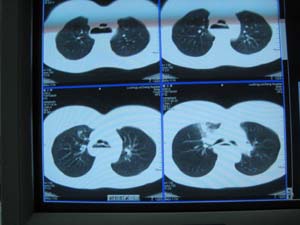

以下是引用xizhong在2009-4-2 7:32:00的发言:[br]右肺中叶不胀,感染所致(中叶综合症)。

以下是引用当兵的在2009-4-1 23:13:00的发言:[br]右肺中叶不张合并感染,建议支气管镜检查。[br]食管呈大萝卜根,贲门失迟缓,